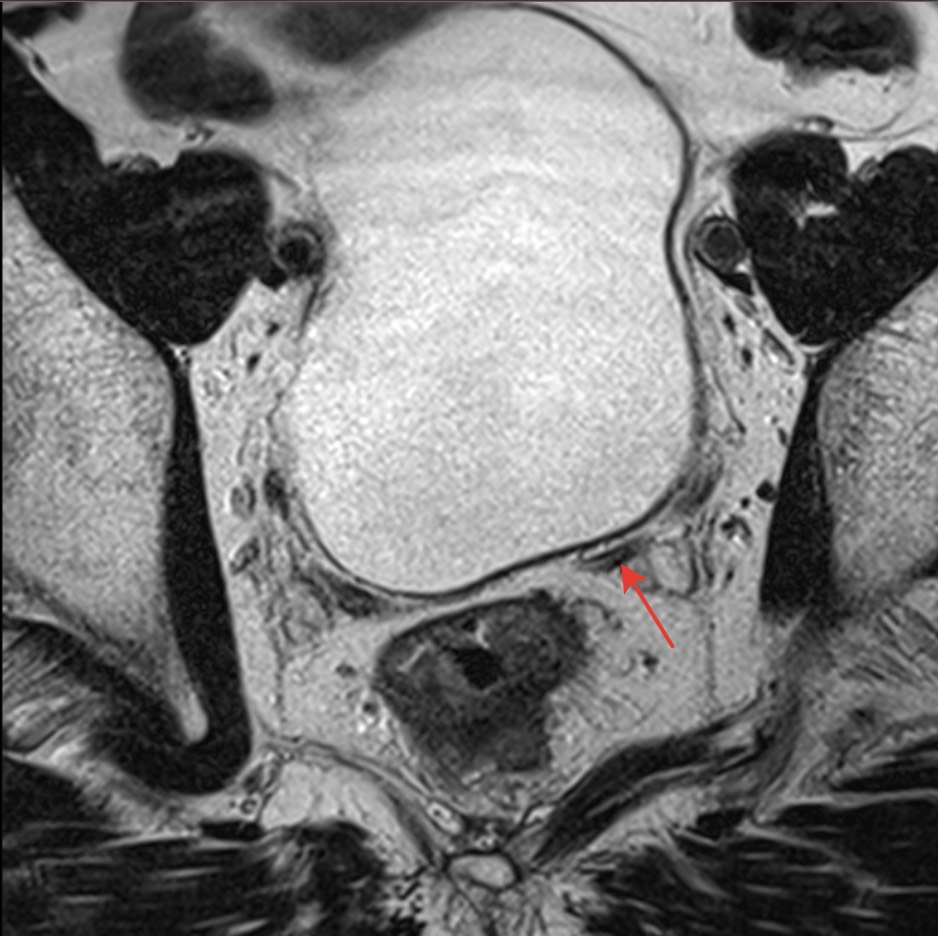

2900. На представленных мр-томограммах органов малого таза стрелкой указан